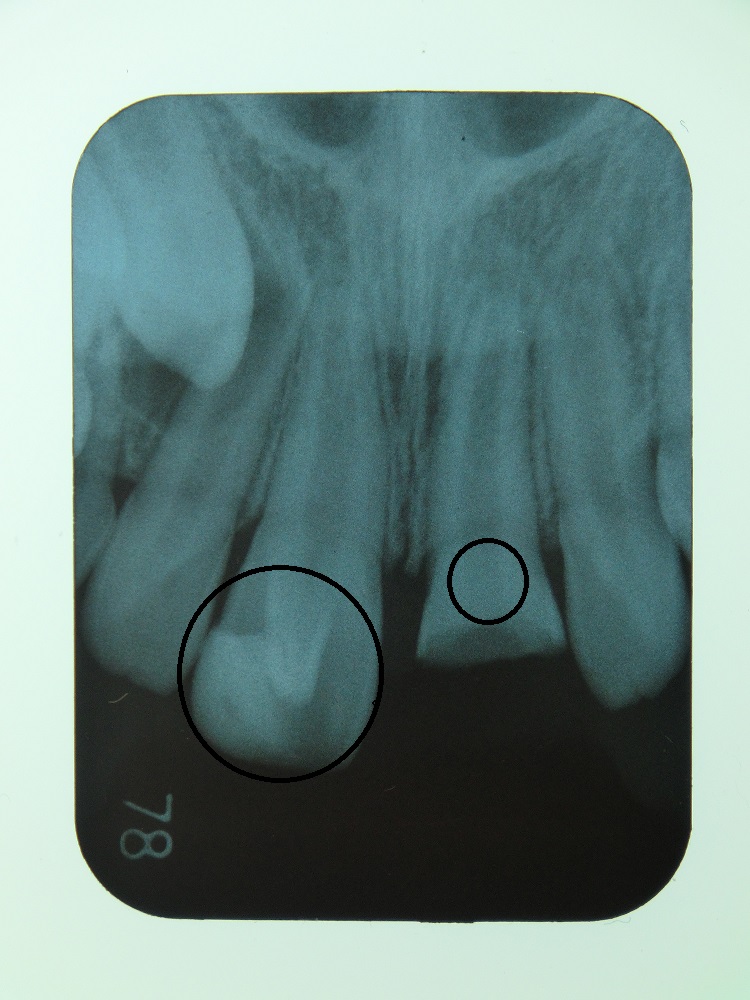

CASE1

小学2年生の女の子のケースです。遊んでる時に転倒し前歯が折れたという事で来院されました。お母さまが来院時、何とか抜かずにして欲しいとの事で折れた歯を持参されていました。根尖が未完成の為、歯髄を1/3切除してMTAセメントで処置後、持参してもらった歯を接着性レジンで修復しました。前歯部なので術後に変色の少ないタイプのMTAセメントを使用しています。実は、半年前にも同じ様に転倒され左上の前歯も破折し修復しています。